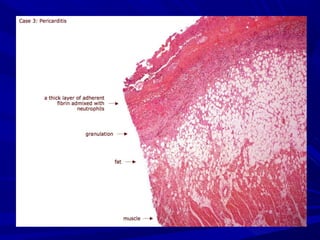

MORPHOPATHOLOGYMORPHOPATHOLOGY

Acute inflammationAcute inflammation

Fibrin depositsFibrin deposits

Increased vascularisationIncreased vascularisation

+/- pericardial fluid+/- pericardial fluid

AdherenceAdherence

+/- myocarditis (CPK , trop)+/- myocarditis (CPK , trop)